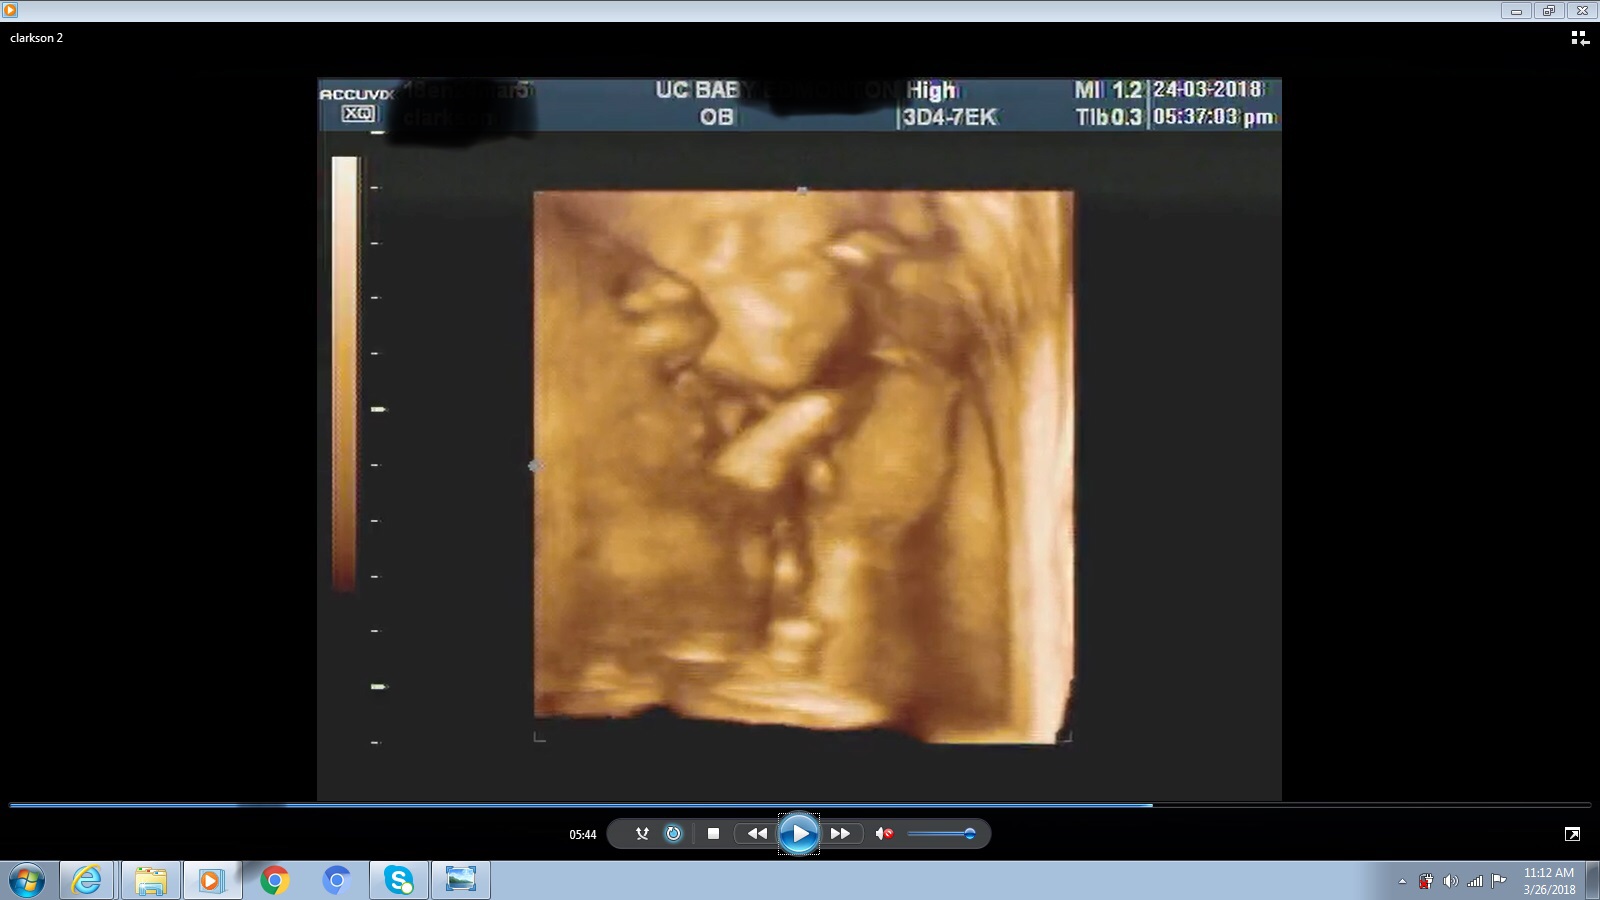

I had a 3D ultrasound at 20 weeks, the tech said boy. She showed me the penis however I forgot to ask to see the scrotum as well nor did I see a potty shot. Can you confirm this is a boy please?Attachment 39128Attachment 39129Attachment 39130